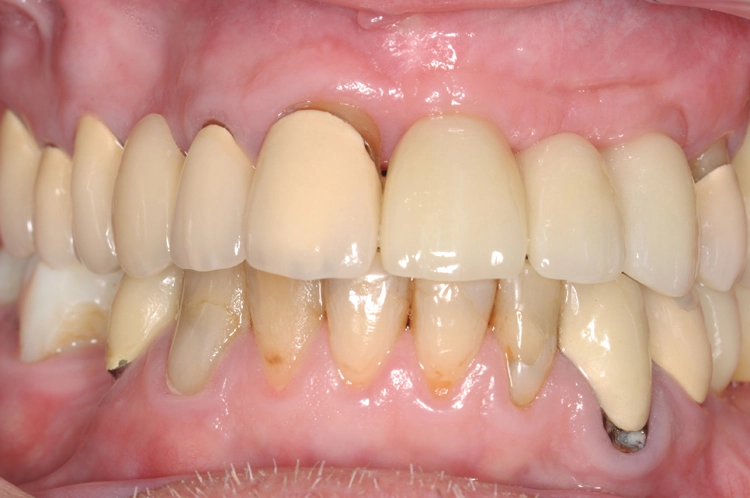

Die Abbildungen 16 und 17 stellen nachfolgend den Zeitpunkt der postoperativen Kontrolle nach dem Einbringen von individualisierten Gingivaformern und die Situation vier Wochen postoperativ dar. Das gelungene Ergebnis der Behandlung nach Alloschalentechnik, Implantation inklusive augmentativem Relining und prothetischer Versorgung zeigen die Abbildungen 18 bis 20.